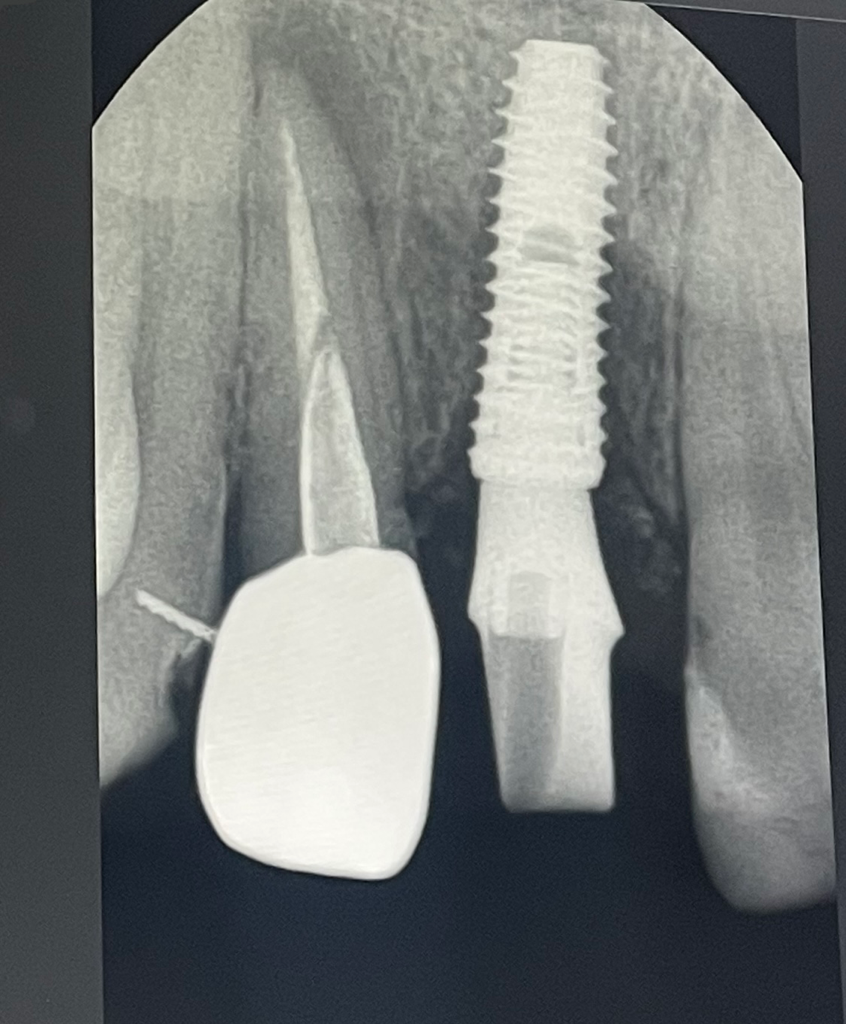

크라운을 한 #12번 치아 치근단 부위에 병소가 보입니다.

병소는 근관내의 감염이나 치근 파절로 인해서 생길수 있습니다.

근관내의 감염이라면 신경치료를 해볼수 있습니다.

치큰에 금이 가다면 발치를 해야 하는경우도 있습니다.

치아뿌리 끝의 염증 사이즈가 큰 편에 속합니다. 이런 경우 재신경치료 후 염증 직접 긁어내는 수술하기도 합니다. 수술 까지 하고도 안되면 뽑고 임플란트 해야 합니다.

말씀하시는 사진으로 보았을 때는 재신경치료를 하셔야 할 것으로 보입니다. 다만 재신경치료 성공률은 매우 낮으며 해당 부위의 염증이 사라지지 않을 수 있습니다. 보통 재신경치료를 할 때는 발치까지 염두해두셔야 합니다. 현재 상태에서는 시간이 지나면 염증이 더 커질 것으로 보이며 치료는 하셔야 할 것으로 보입니다.

염증의 정도는 심한 편이며 크라운을 벗긴 후 재신경치료를 하셔야 합니다.

현재 상태로는 재신경치료하시면 회복될 수 있어 보입니다.